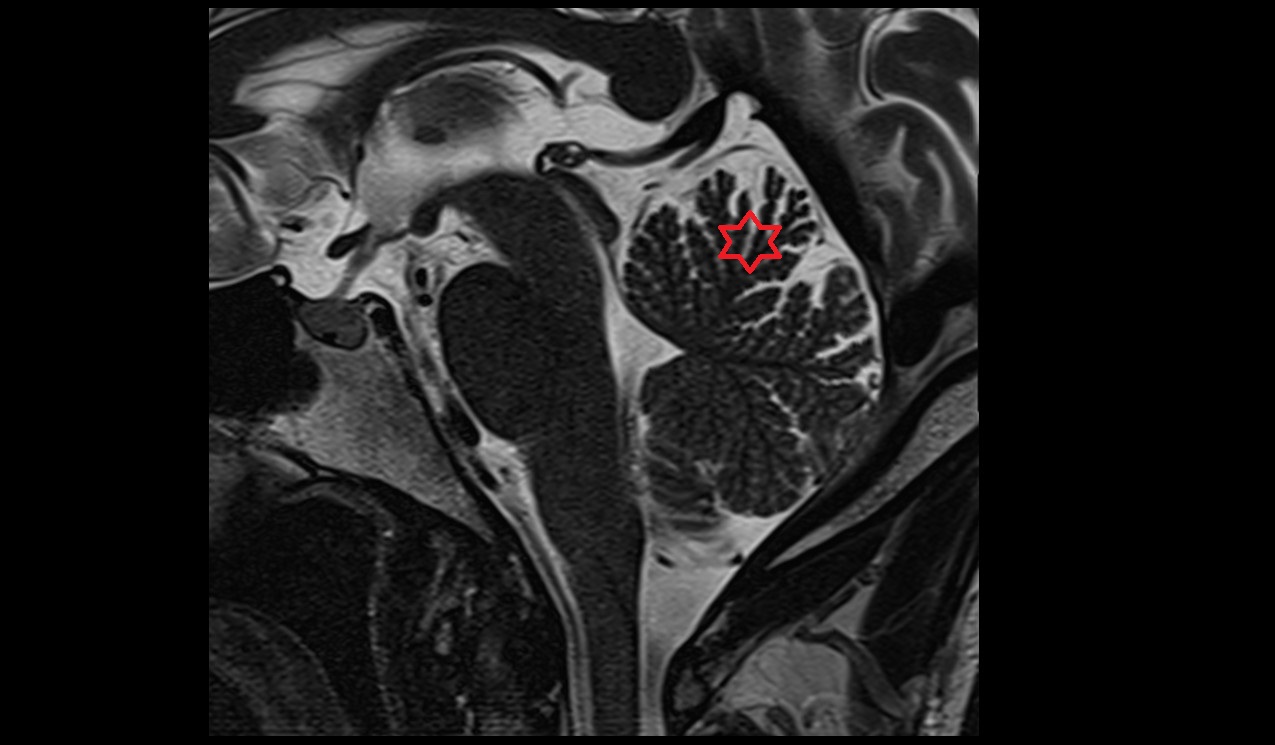

- Fetal cerebellum